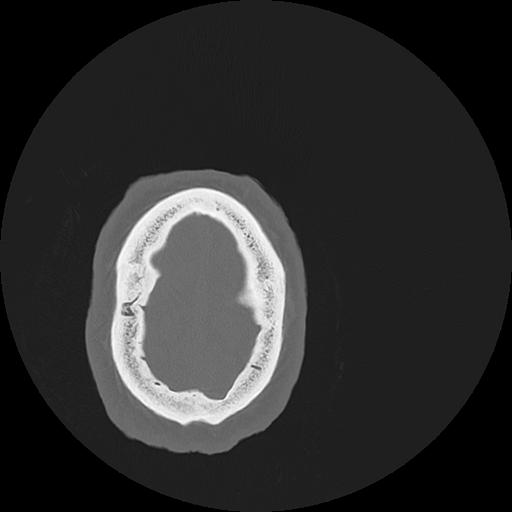

7 HUESO,,Vol,0.5,HUESO,,